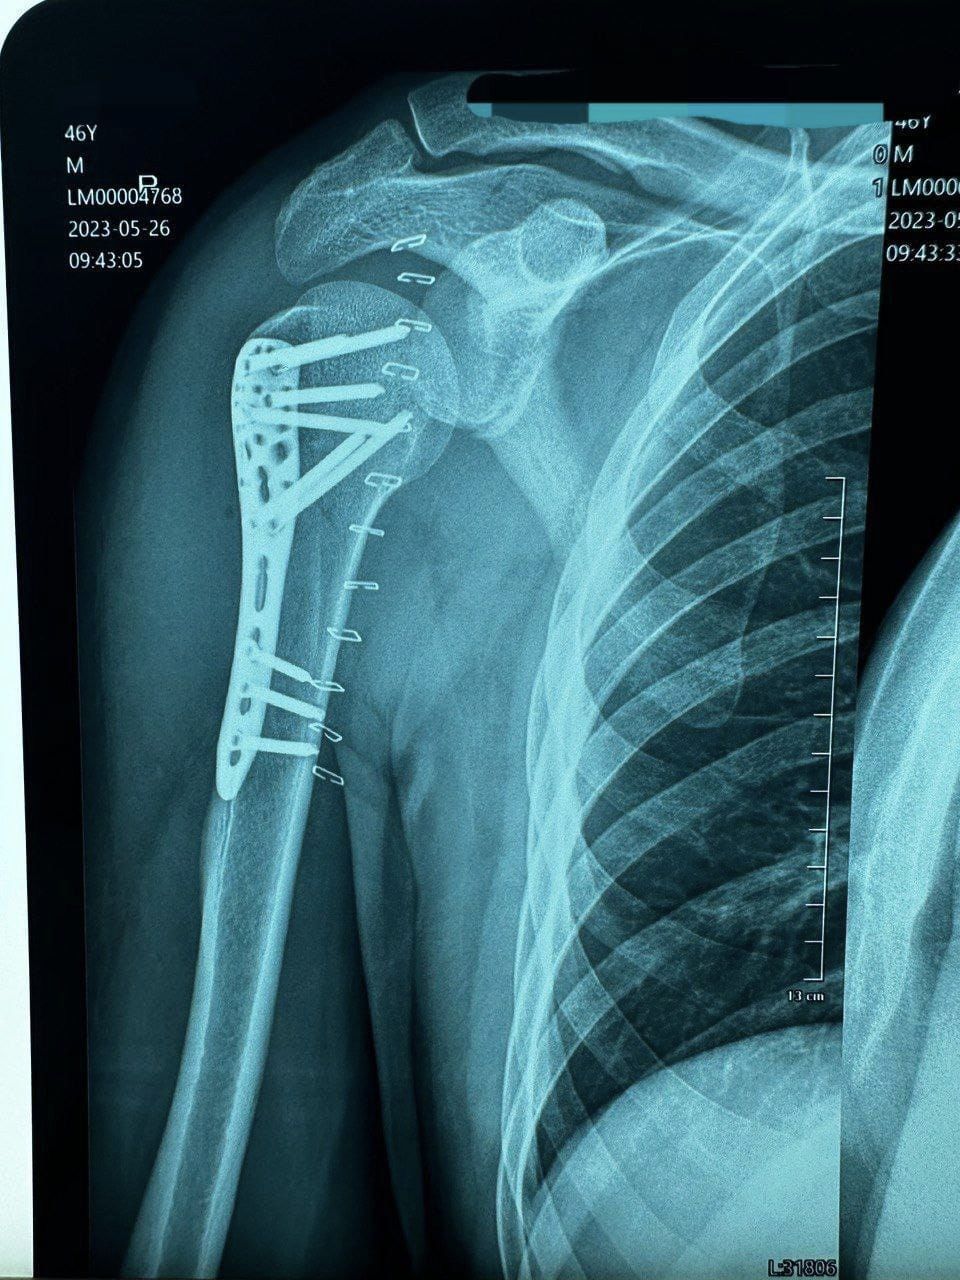

Для лікування переломів кісток верхніх та нижніх кінцівок наших воїнів один з медзакладів Волині отримав комплекти металофіксаторів – пластини із титанового сплаву з гвинтами до них. Їх закупив на 250 тисяч гривень благодійний фонд «Сучасна Україна».

Як розповів представник шпиталю, який одержав обладнання, титанові пластини ставляться у випадку перелому кісток, аби її відновити та зберегти рухливість. Це обладнання значно пришвидшує час реабілітації пацієнта.

«Хлопці починають раніше рухатися, їм потрібно менше часу на реабілітацію і набагато швидше повертаються в стрій. Також набагато покращується якість життя пацієнта, – зазначив в.о. начальника травматологічного відділення, капітан медслужби Дмитро Земба. – Титан інертний до м’яких тканин та не окислюється. Тому, якщо титанові пластини не заважають пацієнту, їх можна не діставати. Також навантаження на кістки буде меншим, якщо пластину не забирати».

Він додав, що такі пластини щодня необхідні у роботі. Це розхідний матеріал, який постійно треба поновлювати у медустанові.

«В основному ці пластини будуть використовуватися для заміни методів фіксації пораненим військовослужбовцям, – розповів медпрацівник. – Вдячні, що продовжуєте нас підтримувати і цінуємо вашу допомогу».